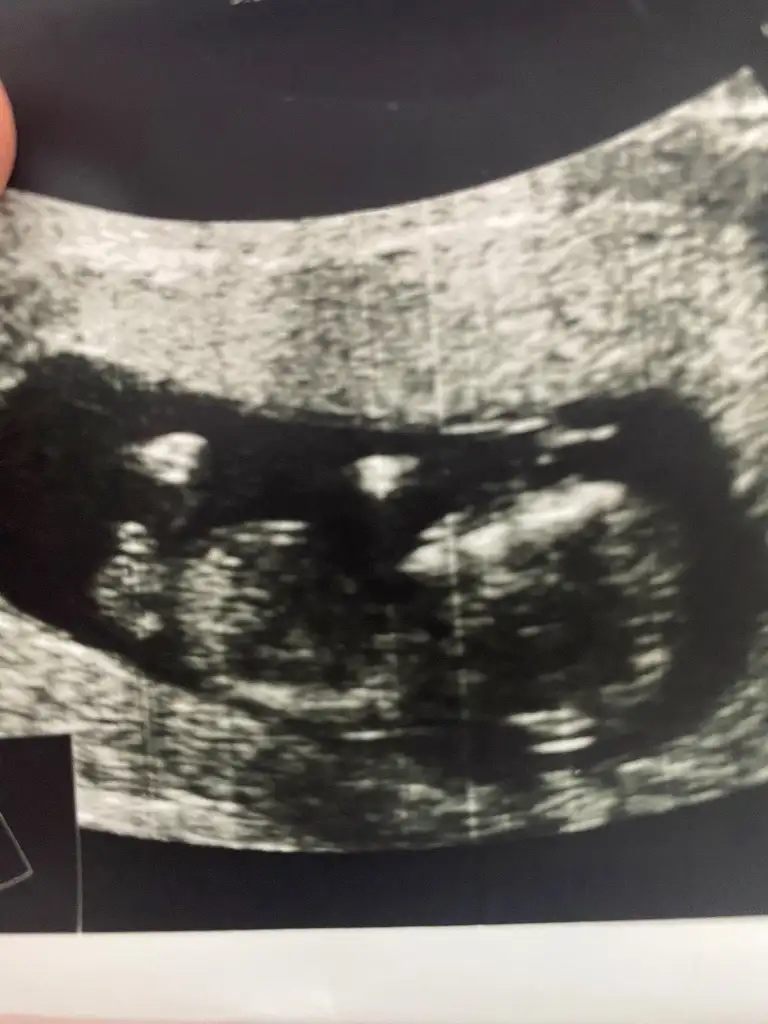

Lütfen bana da bir yorum yapar mısınız. Karından. 13+4 haftalık. İki kızım var erkek olsun istiyorum 🙈

• IMG_20250307_073925.webp

IMG_20250307_073925.webp

22,9 KB · Görüntüleme: 150